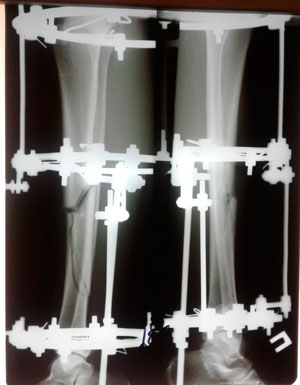

Исходник -43 года.

Дата операции - 18.07.2019г.

Диагноз: нетипичная варусная деформация голеней, на границе нижней и средней/3

Исправление по методике доктора Онипко Н.Н.